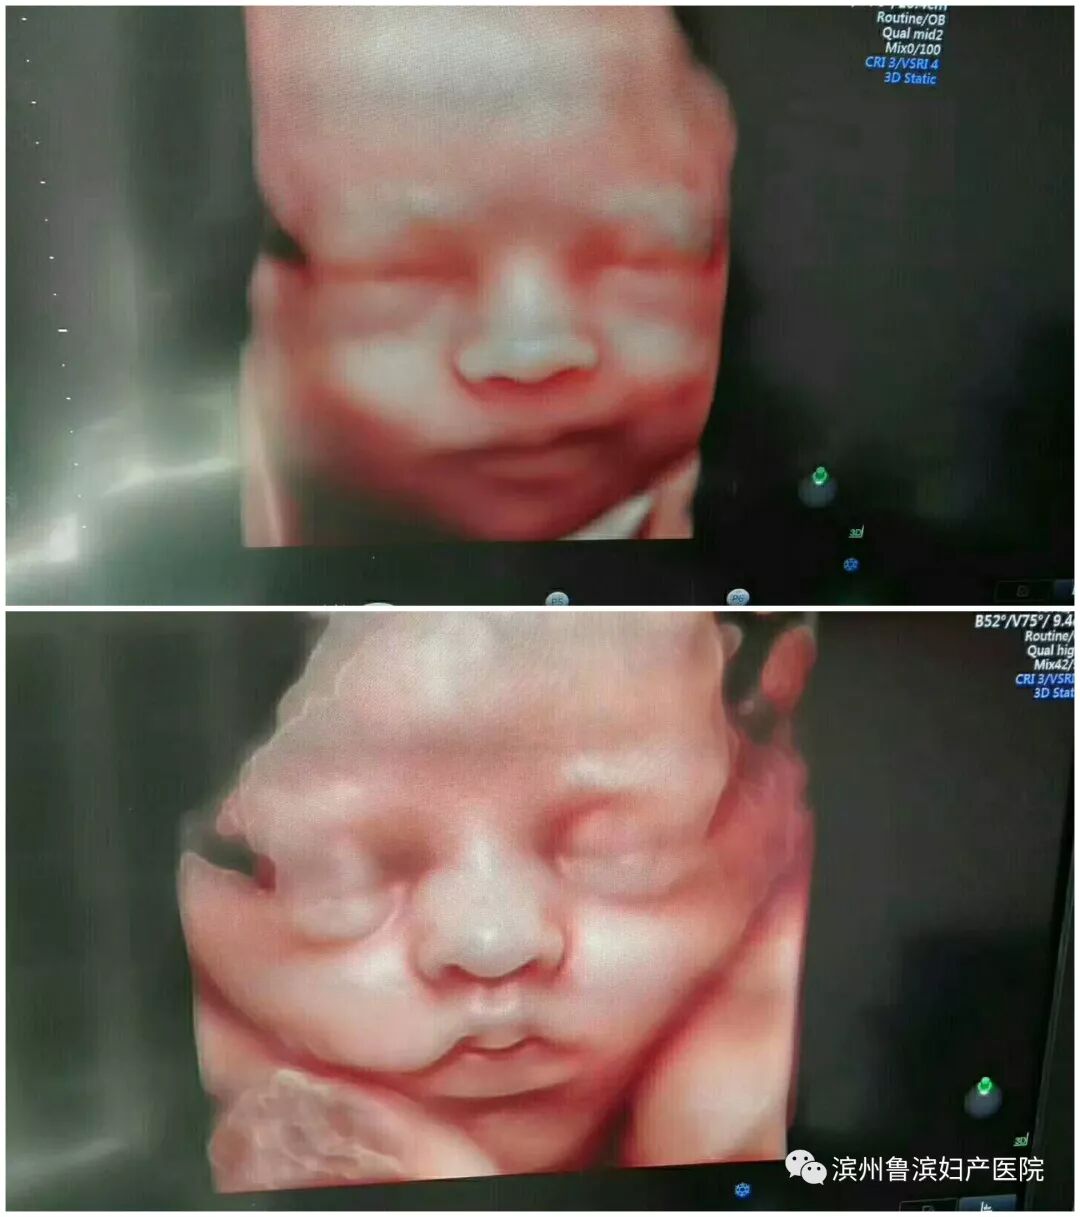

★美国GE E10高清四维彩超自动为胎儿拍宫内“写真”和动态录像